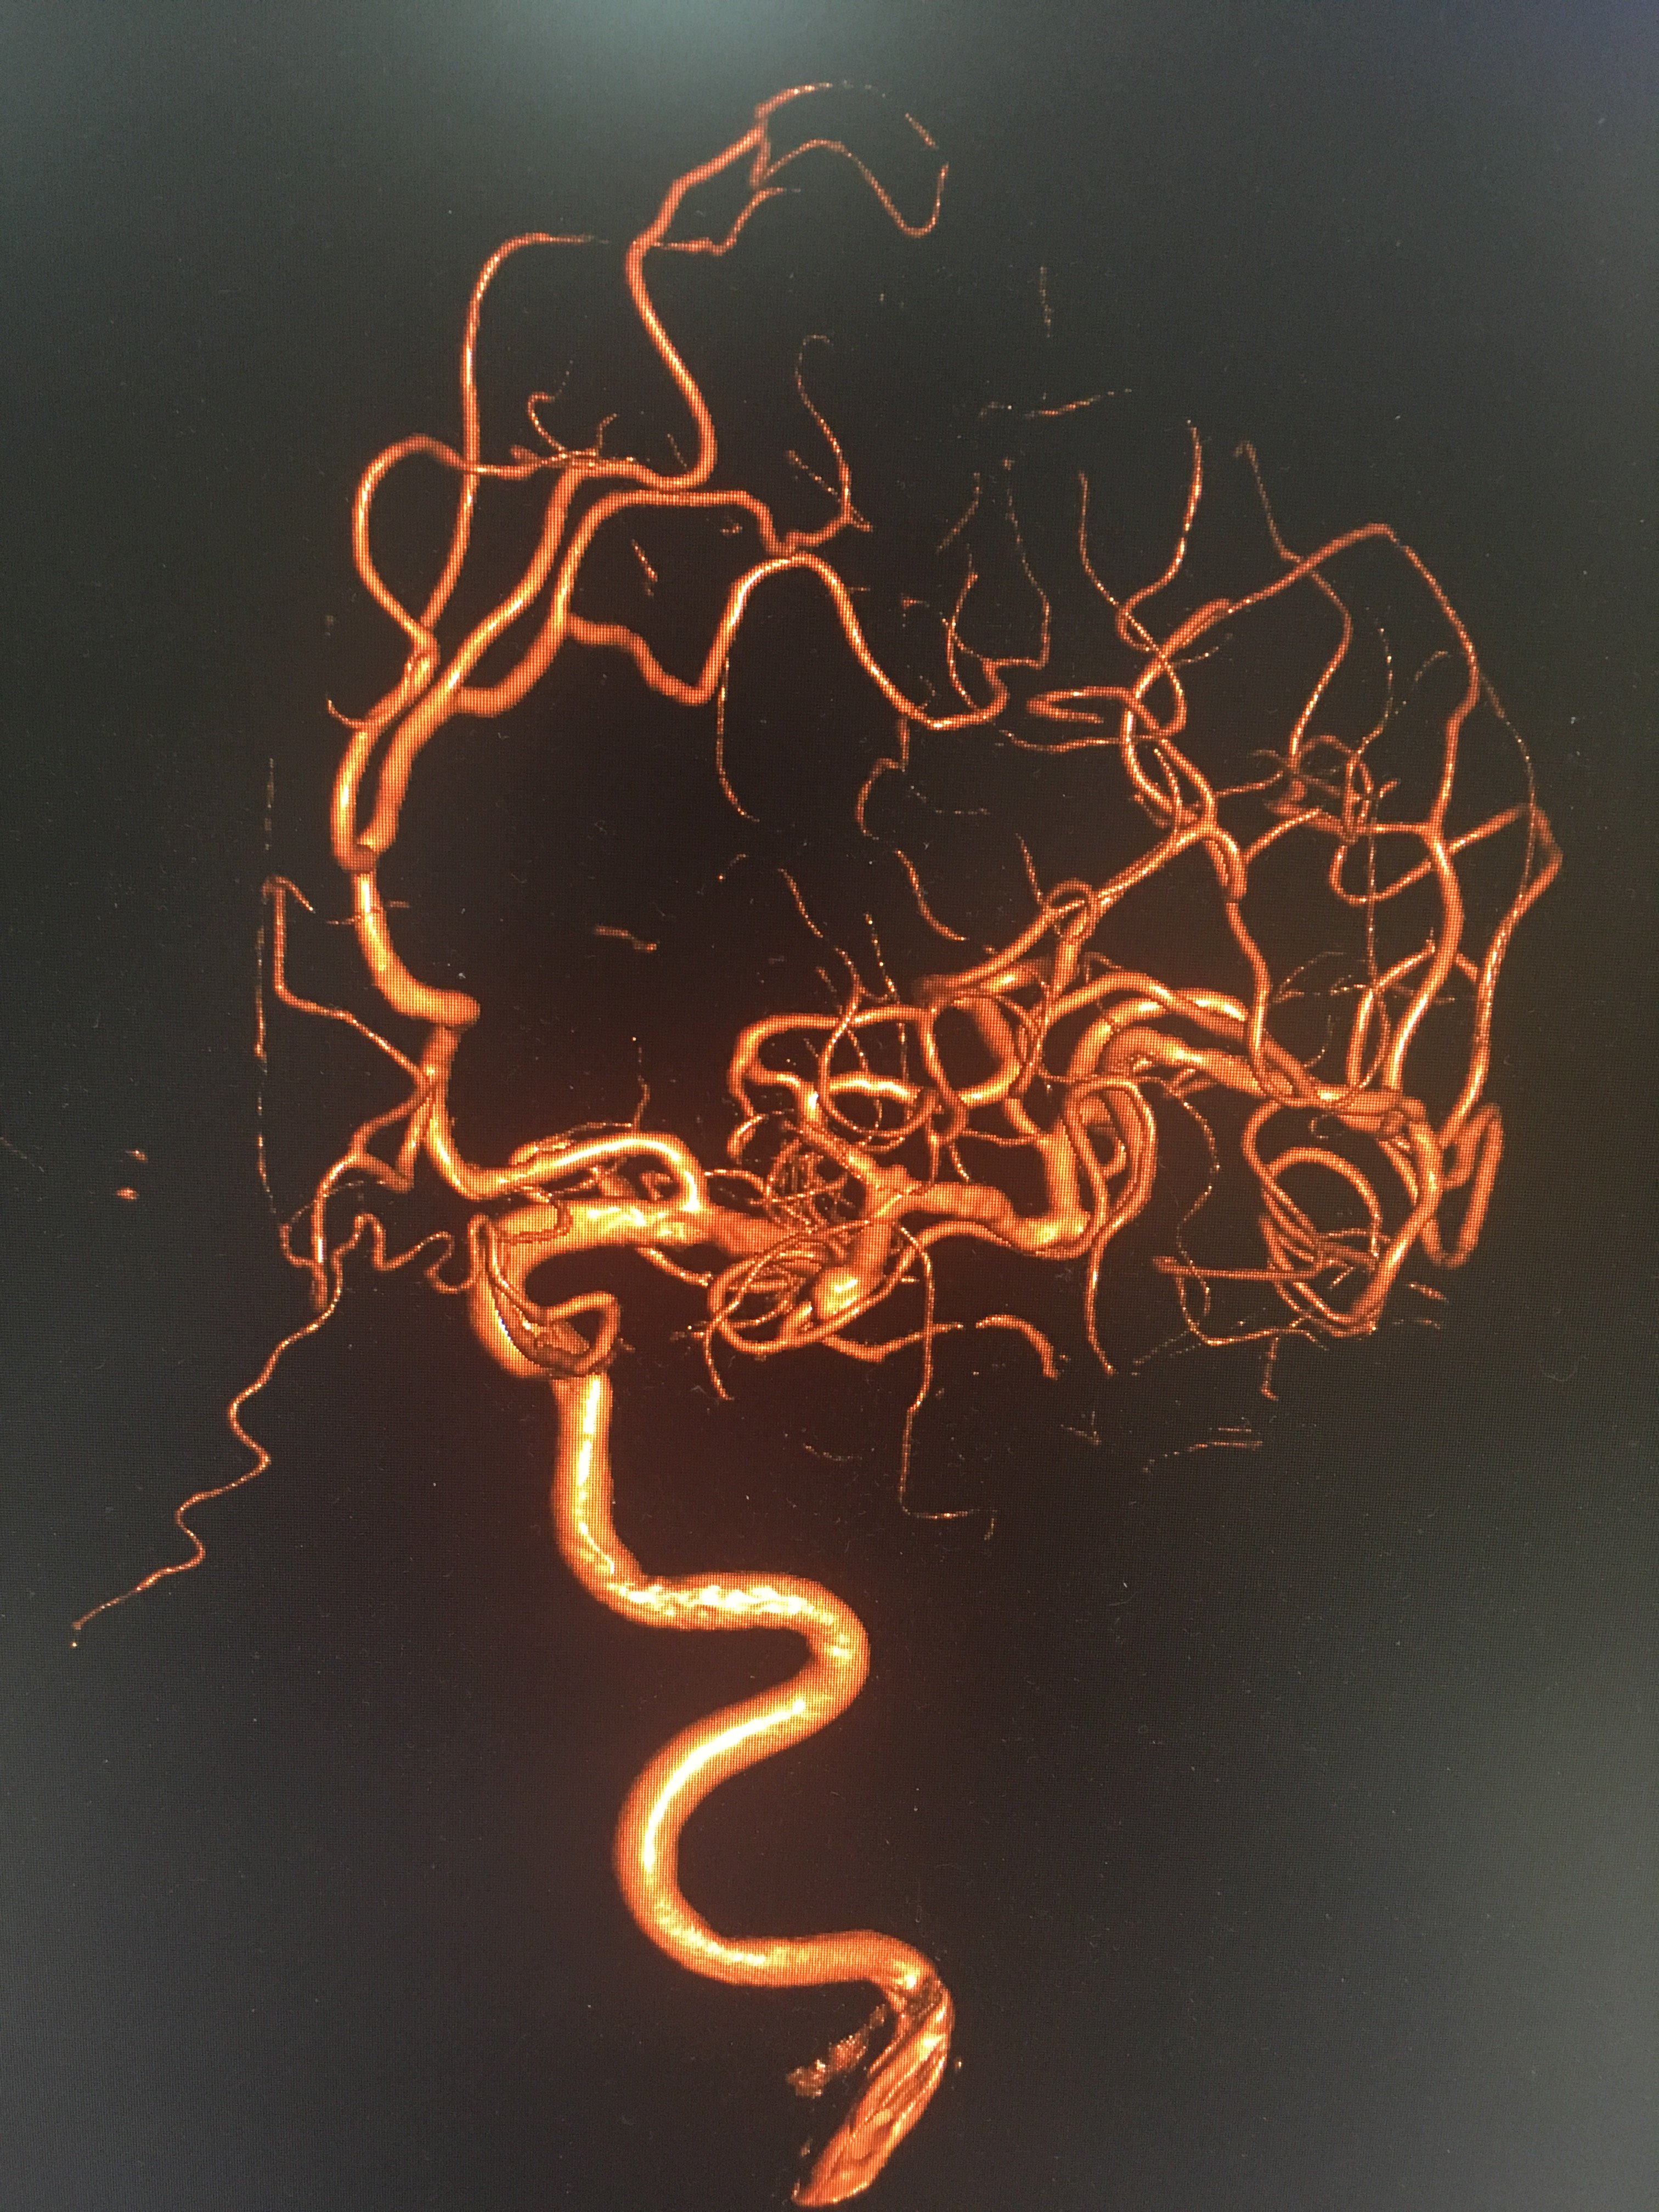

王洪荣,左侧大脑中动脉动脉瘤.